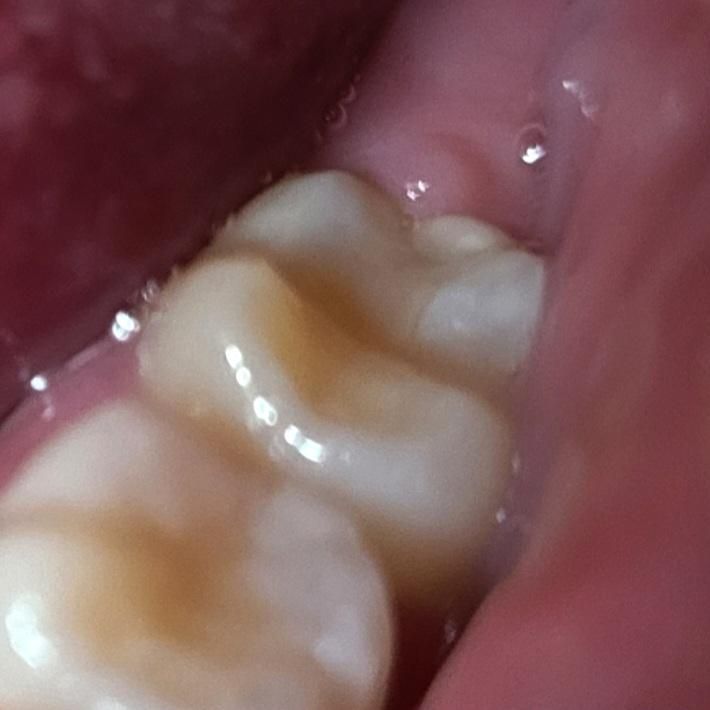

어금니 인레이 옆 틈 보임(치아 실금?)

(동그라미 표시한 부분)

어금니와 인레이 사이에 틈이 보이고, 틈 옆의 일부 치아가 불투명하고 동그란 모양으로 보이는데요...(제가 보기엔 동그랗게 실금이 생긴 것처럼 보여요) 통증은 없어요

치료받았던 치과에 상황 설명했더니 통증없으면 냅둬도 된다고 해서 일단 지켜보려는데, 좀 신경쓰여서 이정도는 괜찮은건지 글 올려봅니다

치료한지는 1년 정도 되었습니다

인레이의 경계부위가 저렇게 보이는거 같습니다. 걸리는 부분이 잇다면 부드럽게 다듬으면 될것같습니다.

인레이와 치아 사이 경계가 보이는 것은 자연스럽고 괜찮습니다. 다만, 경계 옆 부위 치아가 혼탁한 흰색을 보이는 것은 초기 우식의 가능성이 있으니 치과가서 체크해보시기 바랍니다.